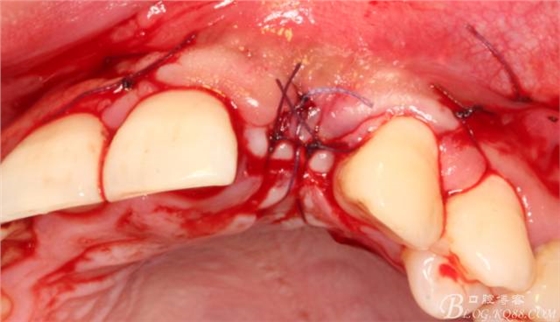

于是我果斷告知患者,手術(shù)失敗了,不能拖延,如不及時(shí)處理,炎癥繼續(xù)發(fā)展會(huì)很快波及鄰牙牙槽骨?;颊呓邮芪业慕ㄗh。切開(kāi)翻瓣,骨粉及生物膜消失了,骨吸收嚴(yán)重,幸運(yùn)的是,因?yàn)樘幚砑皶r(shí),鄰牙骨支持依然存在。

徹底掻刮。